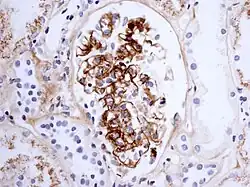

Os portadores de NIgA apresentam aumento do nível sérico de imunoglobulina A por déficit de excreção hepática ou aumento de sua síntese na medula óssea. A lesão renal é secundária à deposição dessa imunoglobulina nas estruturas glomerulares. Deve-se suspeitar de glomerulonefrite quando a ureia em urina é 30 vezes maior que a creatinina em urina. Quando se detecta sangue e proteínas na urina pode-se pedir uma biópsia renal para identificar a causa. O achado anátomo-patológico da biópsia renal mais característico é a deposição de IgA no mesângio.[3]